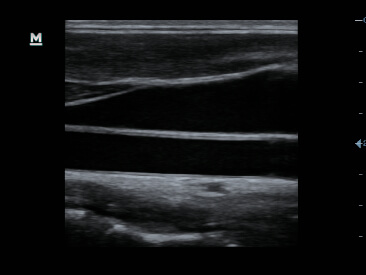

GI solution:iScape View and Auto IMT package

Clinical Images

-CCA & Jugular vien

-Brachial plexus